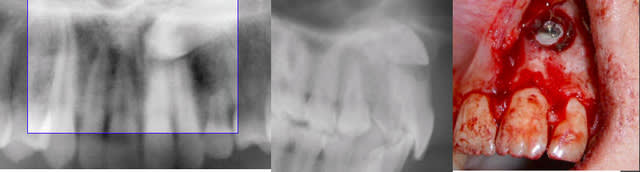

Oui, c'est juste, vous avez raison.

C'est très simple quand on a une radio de profil en plus de l'OTP (les 2 clichés basiques d'un bilan orthodontique) : une canine palatine y apparait verticale et une canine vestibulaire horizontale, couronne vers l'avant, comme sur l'exemple que je vous joins avec les confirmation chir.

Il n'y a que pour les cas relativement peu fréquents où elle est entre les 2 qu'il est souhaitable d'avoir un examen complémentaire.

Daniel